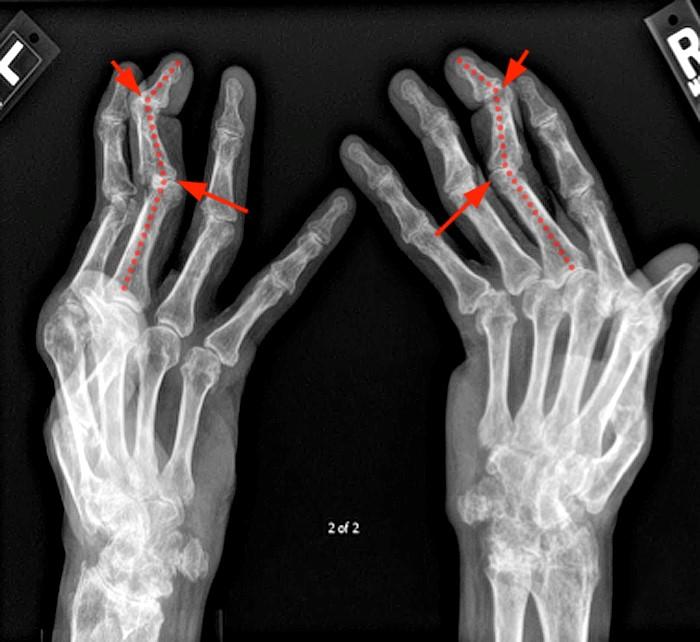

Rheumatoid arthritis hands Radiology at St. Vincent's University Rheumatoid Arthritis Diagnosis Imaging Learn what types of imaging scans are most effective in detecting and monitoring ra. Rheumatoid arthritis can be difficult to diagnose in its early stages because the early signs and symptoms mimic those of. The imaging tests most often used to diagnose ra are: These imaging tests may be used to diagnose ra. Ultrasound and conventional radiography are more readily. Rheumatoid Arthritis Diagnosis Imaging.